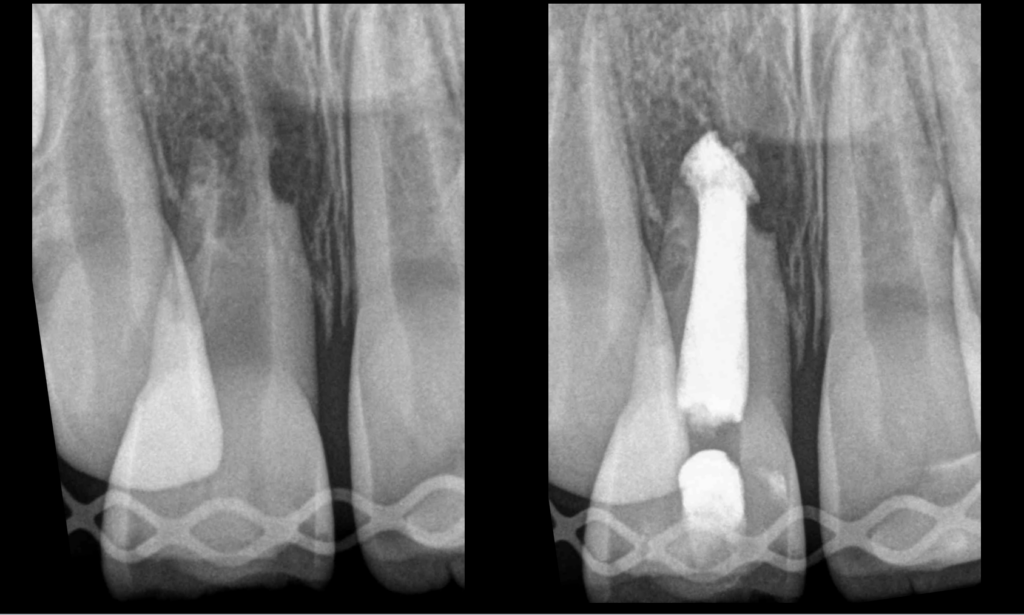

🔍 Jeune homme de 7,5 ans.

ATCD de traumatisme dentaire.

Pulpe nécrosée

Parodontite apicale asymptomatique

Résorption radiculaire externe inflammatoire apicale et latéro-radiculaire.